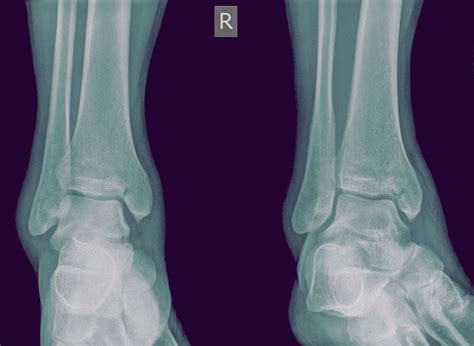

Diagnosing a Medial Malleolus Fracture

Diagnosing a Medial Malleolus Fracture involves a combination of physical examination and imaging tests. The process typically includes:

• Physical Examination: A healthcare provider will assess the ankle for swelling, tenderness, and deformity. They may also check the range of motion and stability of the joint.

• X-Rays: The primary imaging tool for diagnosing fractures. X-rays can show the location and severity of the fracture.